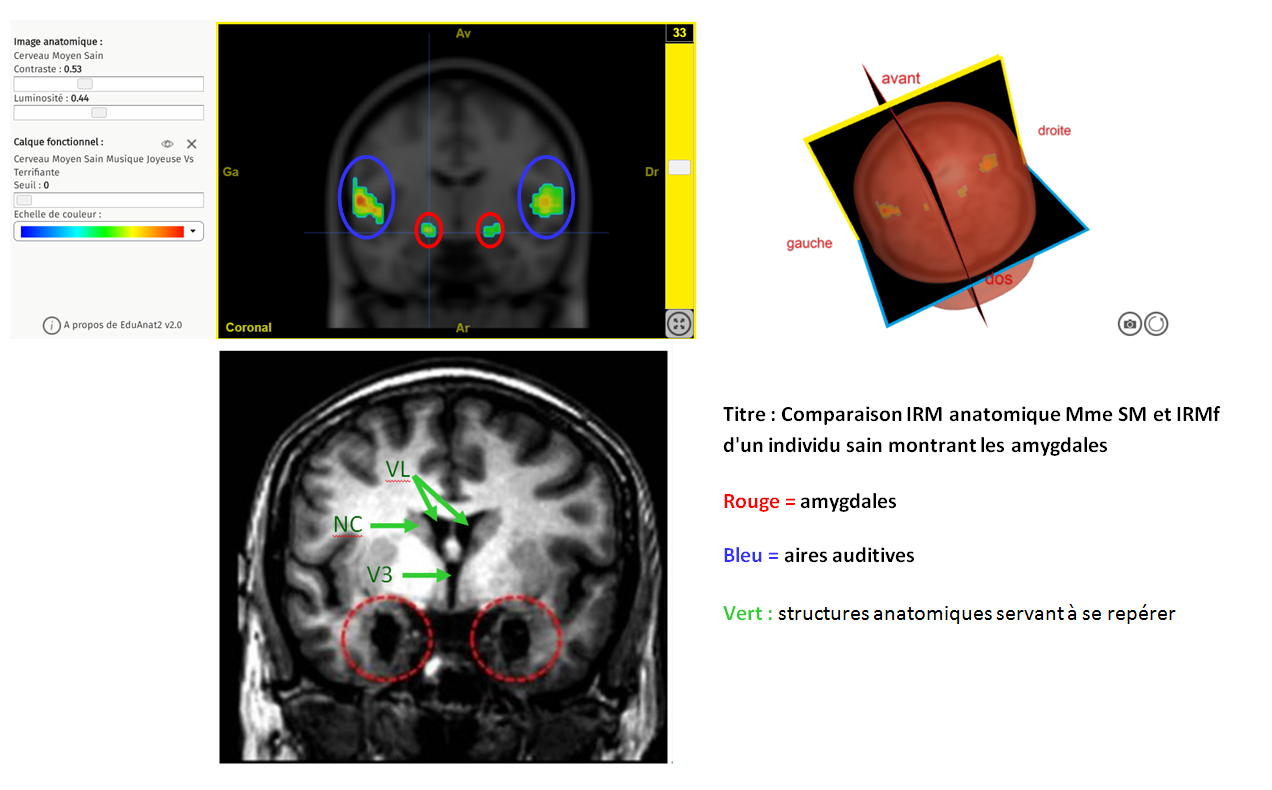

STRESS COMPARAISON sm AMYGDALE